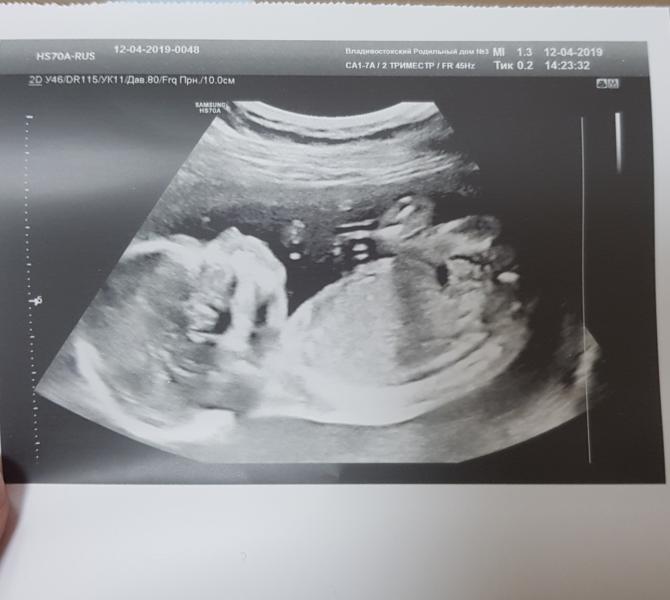

Мальчик у нас😊Чернухина делала,меня ничего не смутило,сделала всё хорошо. Рожаем 5 сентября.